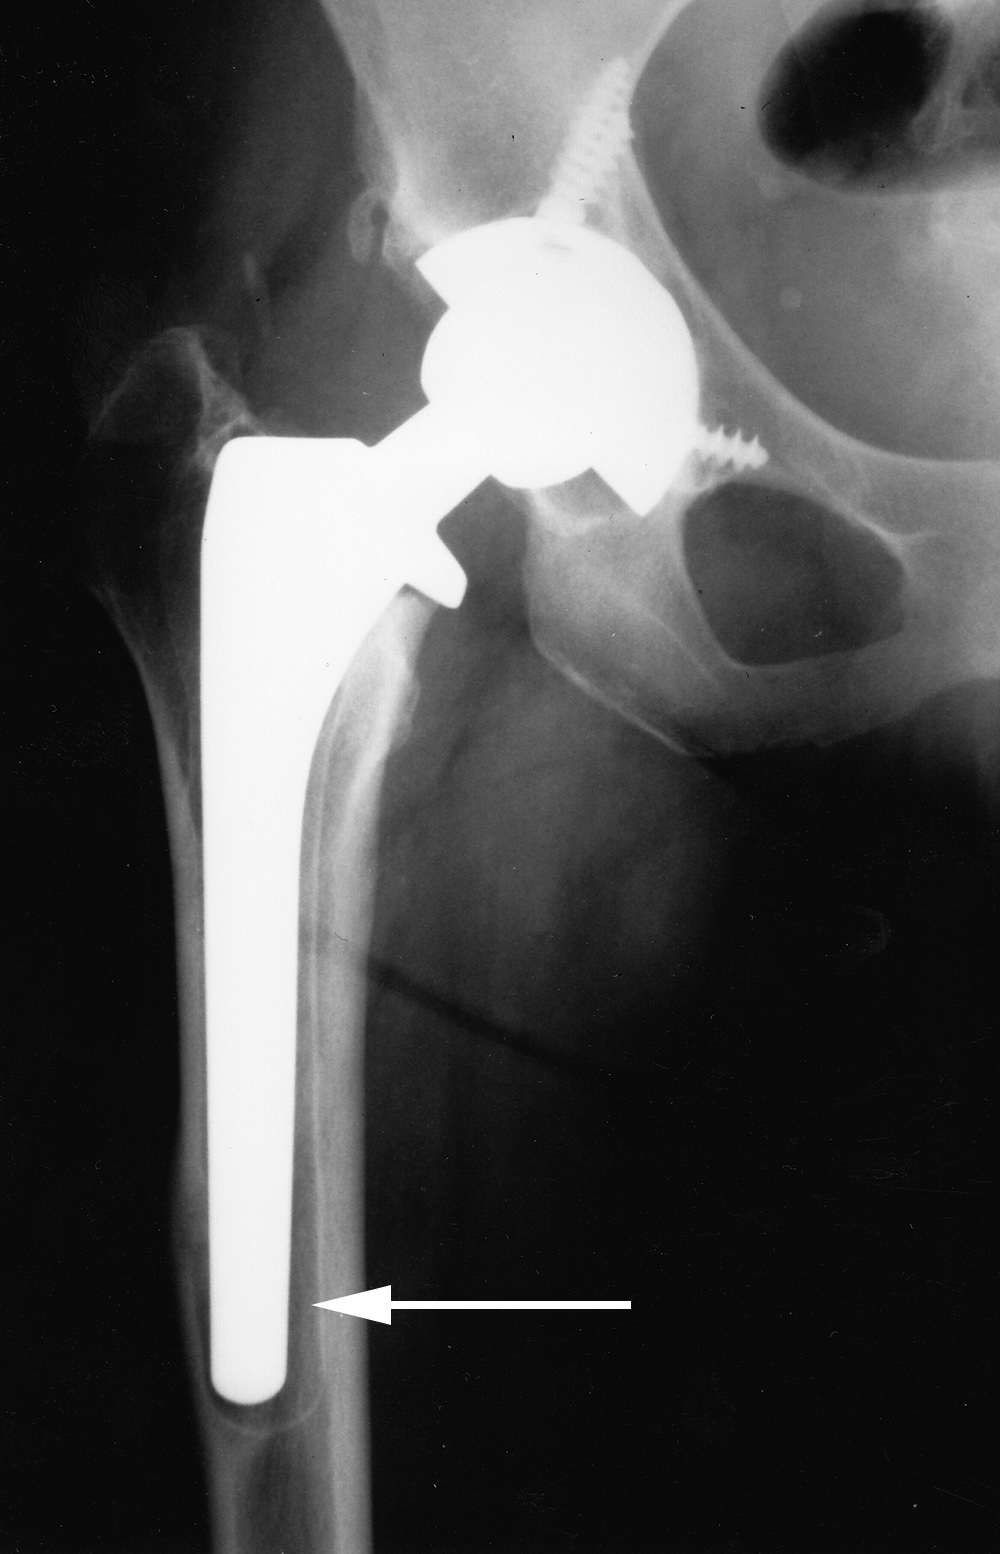

or cement-bone interface. Progressive development of radiolucent areas greater than 1 mm at these interfaces is worrisome for prosthesis loosening (figure: osteolysis at tip of femoral stem).

| Cemented total hip arthroplasty with focal osteolysis about the stem in zones, 2, 5, and 7. From Benjamin, 1994 |

There is radiolucency (arrow) around the entire femoral stem with a sclerotic margin and eccentric positioning of the stem. There is also thinning of the lateral femoral cortex. From Benjamin, 1994 |